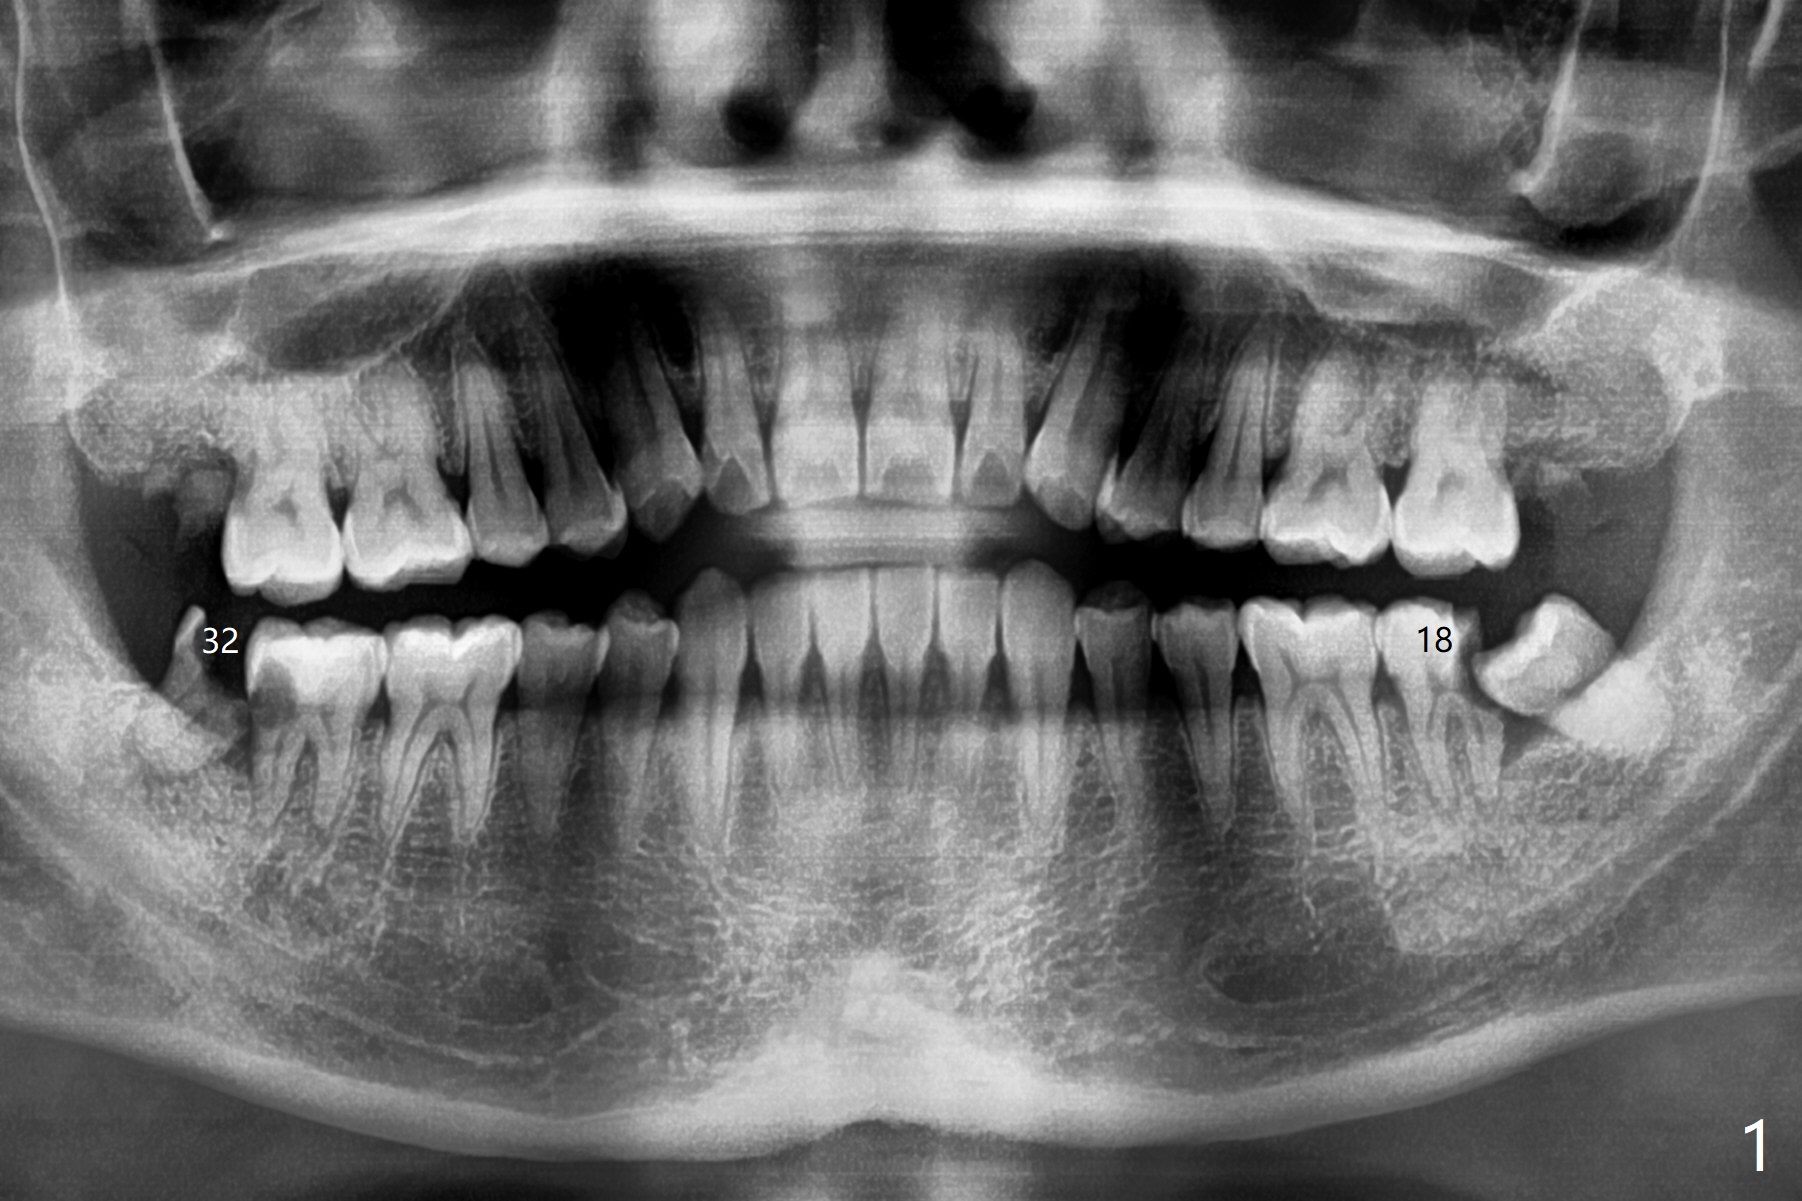

A 36-year-old man with poor dentition (smoker 1/4 ppd) requests extraction of sympto-matic teeth (#18 and 32, Fig.1). A half of Osteogen Plug is placed at #32 post extraction. To extract #18, the tooth has to be sectioned (Fig.2 red). The mesial portion is removed easy, while the distal one requires removing the mesial surface of #17 (Fig.2 green). Vanilla bone is placed after extraction (Fig.3), covered by 8x8 mm Amnion-Chorion Allograft and sutured with 4-0 PGA. Four months later, the mesial surface of #17 will be trimmed (Fig.4 black area) so that surgical guide metal sleeve (green) will be seated in the neutral position of the edentulous area. After extraction (Fig.5 black), the distal portion of the mesial crest will be resorbed, leading to gingival papilla atrophy and food impaction (Fig.6). Keeping the mesial portion of the root (Fig.7 *, socket shield) is able to prevent mesial crestal bone loss. The immediate implant will be placed ~ 2 mm short of the depth and checked whether it touches the retained root or not.